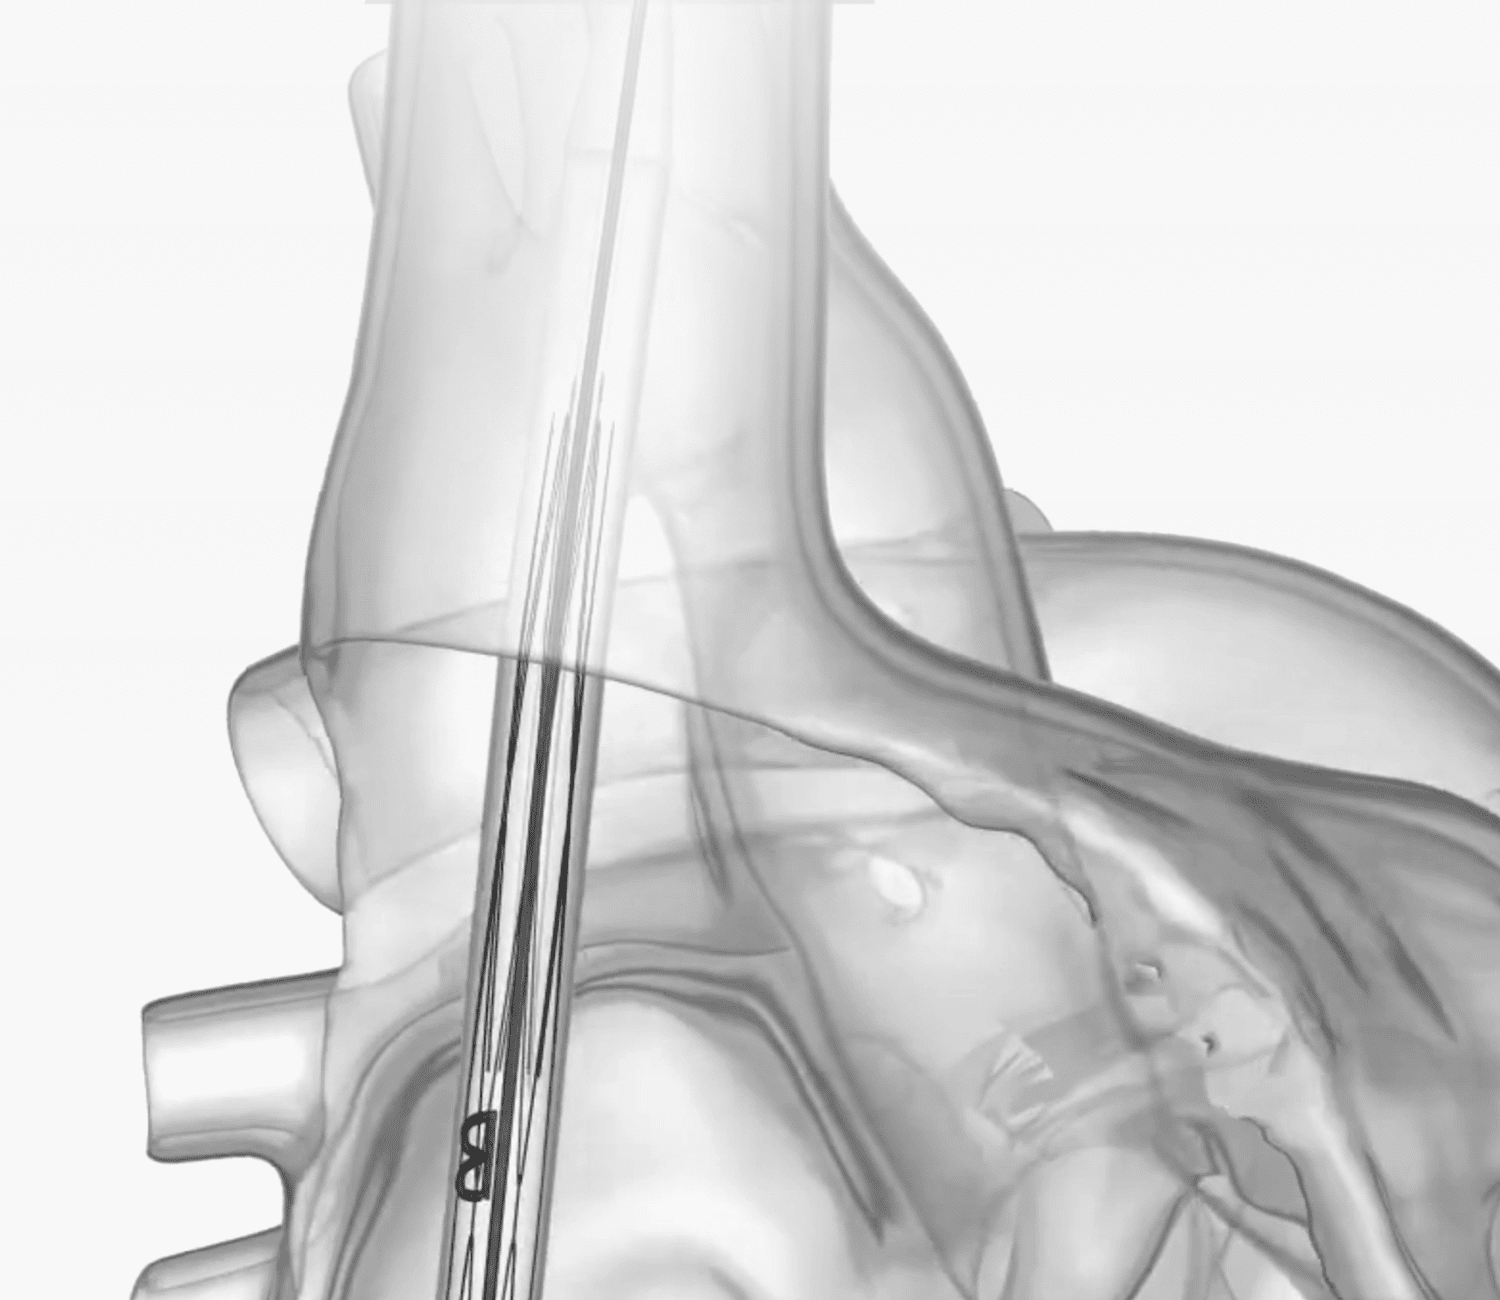

Short Implantation

Procedure

Device time of less

than 10 minutes

Secure Positioning

Engineered for

highly reliable

migration resistance

Reliable Sealing

Preventing caval

backflow while allowing

hepatic vein inflow

Mechanically Durable

Designed and tested for

600M cycles with no

fractures or malfunctions

Conscious Sedation

No need for TEE or

general anesthesia (GA)